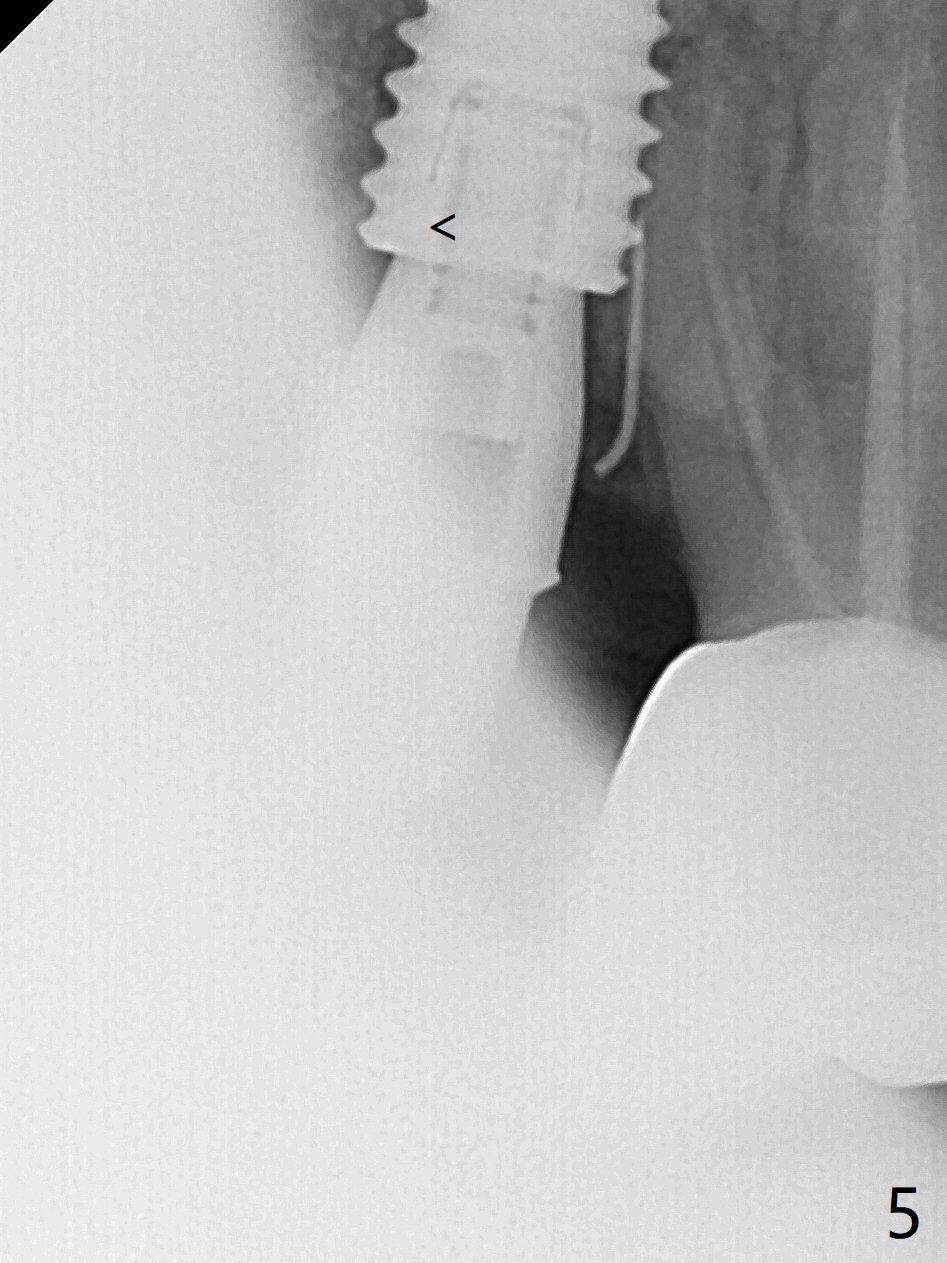

A 55-year-old woman had Hiossen implants (4x13, 5x13 mm) placed at #12 and 14 in China > 6 months (Fig.1,2). The fixtures are placed deep and un-parallel mesiodistally. After SRP UL, the implant at #12 is uncovered, followed by 4.6 and 5.5 mm profile drills and 5.5x7 mm IS healing abutment. The healing abutment at #14 is changed from 5x7 mm to 6.8x7 mm for easy impression later on. Due to coronavirus, the patient returns 8 months later. Oral hygiene is poor. The gingival cuffs at #12 and 14 are erythematous and edematous. UF cemented abutments have to be placed (Fig.3-5) because of equi-gingival fracture of #3 and 4 splinted crowns. In fact the straight abutments are not parallel buccopalatally. Buccoocclusal reduction is done at #12 for provisional FPD. SRP will be performed with #11 DL composite prior to impression.